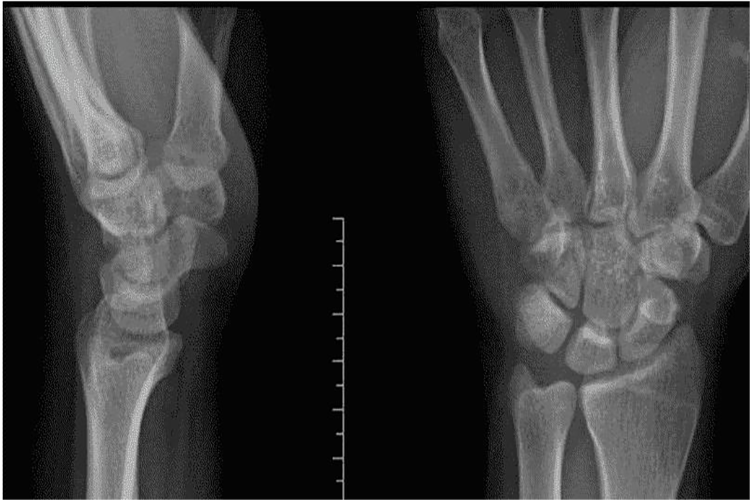

腕关节由桡腕关节、腕骨间关节、腕掌关节组成,在功能上前两个关节构成一个联合关节。

桡腕关节:是典型的椭圆关节,由桡骨的腕关节面和尺骨头下方的关节盘作为关节窝,近侧列的手舟骨、月骨、三角骨的近侧关节面作为关节头而共同构成。手舟骨、月骨、三角骨之间被坚韧的骨间韧带连接在一起,可将它们看成一块骨。三角形的纤维软骨关节盘附于桡骨远侧的尺侧缘,尺骨茎突之间;关节盘的远侧尖端附着于三角骨。

腕骨间关节:腕骨间关节由近侧的三个腕骨(手舟骨、月骨、三角骨)和远侧的四个腕骨(大多角骨、小多角骨、头状骨、钩骨)组成。

腕掌关节:由远侧列腕骨与5个掌骨底构成。拇指腕掌关节是由大多角骨与第1掌骨底构成的鞍状关节。